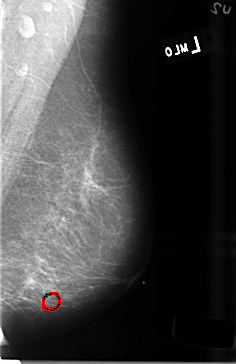

B_3470_1.LEFT_MLO

FILE: B_3470_1.LEFT_MLO.OVERLAY

TOTAL_ABNORMALITIES 1

ABNORMALITY 1

LESION_TYPE CALCIFICATION TYPE PUNCTATE-PLEOMORPHIC DISTRIBUTION CLUSTERED

ASSESSMENT 4

SUBTLETY 2

PATHOLOGY BENIGN

TOTAL_OUTLINES 1

BOUNDARY